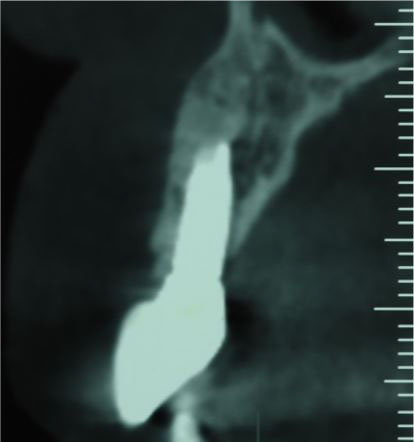

A 48-year-old female patient referred to the clinic interventions, immediate implantation with a complaint of the crown mobility and pain on biting related to the upper right lateral incisor (Figure 1). She was in good general health, and her medical history revealed no medical conditions. Intraoral examinations demonstrated healthy gingival and periodontal status, stable occlusion, acceptable intermaxillary relationship, and no parafunctional habits. Clinical intraoral examinations revealed an oblique complicated crown fracture of the maxillary right lateral incisor. The fracture line extended subgingivally on the labial aspect and ended close to crestal labial bone (Figure 2). Crown lengthening procedure was not a treatment option since it could lead to compromised esthetic outcomes. On the periapical radiograph, the tooth seemed to be an ideal candidate for immediate implant insertion; however, CBCT and clinical evaluations showed a large bone concavity in the apical area of the tooth (Figure 1). After a thorough clinical examination and radiographic evaluation, different treatment plans were explained to the patient. Taking into consideration the maintenance of an esthetic appearance during the treatment procedures and the patient’s desire for a minimal number of surgical the final treatment plan. The apical bone concavity had to be resolved; otherwise, implant placement inimmediate provisionalizatoin was decided upon as an ideal position was not possible; therefore, it was decided to augment the apical bone concavity before tooth extraction and immediate implantation. Prior to the surgical process, informed consent was obtained from the patient.

Figure 1.

(A) The preoperative clinical and (B) CBCT views